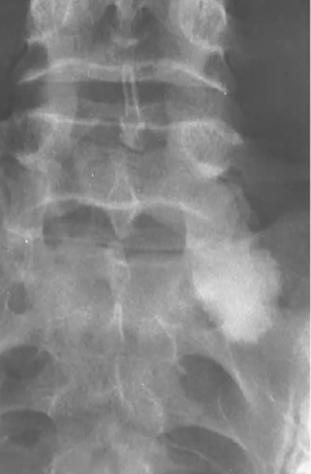

Hémangiome : Bénin mais DOULOUREUX

- 1er plus commune tumeur bénigne de la colonne (squelette axial)

- F > H , > 40 ans

- La majorité des lésions sont dans la colonne

- Colonne : « CORDUROY CLOTH »

- Crâne : « SPOKED-WHEEL APPEARANCE »

- Si apparence de plusieurs hémangiomes, c’est de l’ostéoporose

- DDX : Maladie de paget (mais dans ça, les contours vertébraux sont sclérotique (picture frame vertebrae).